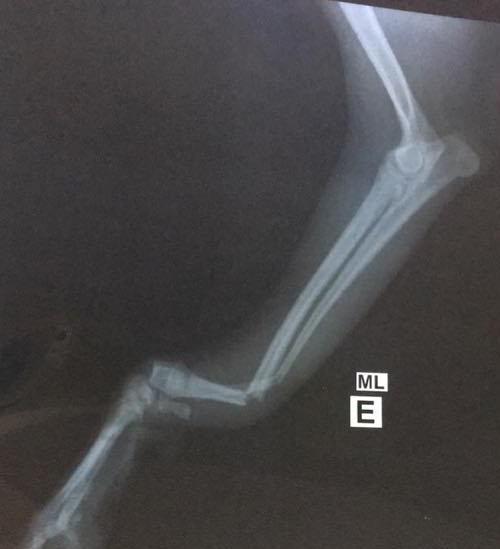

Above Two Photos: Our little guy Arthur broke is leg is two places in the midst of having our family here in Brazil from the States. He had surgery and had a plate and 5 screws place inside his leg. He's healing up and doing great.